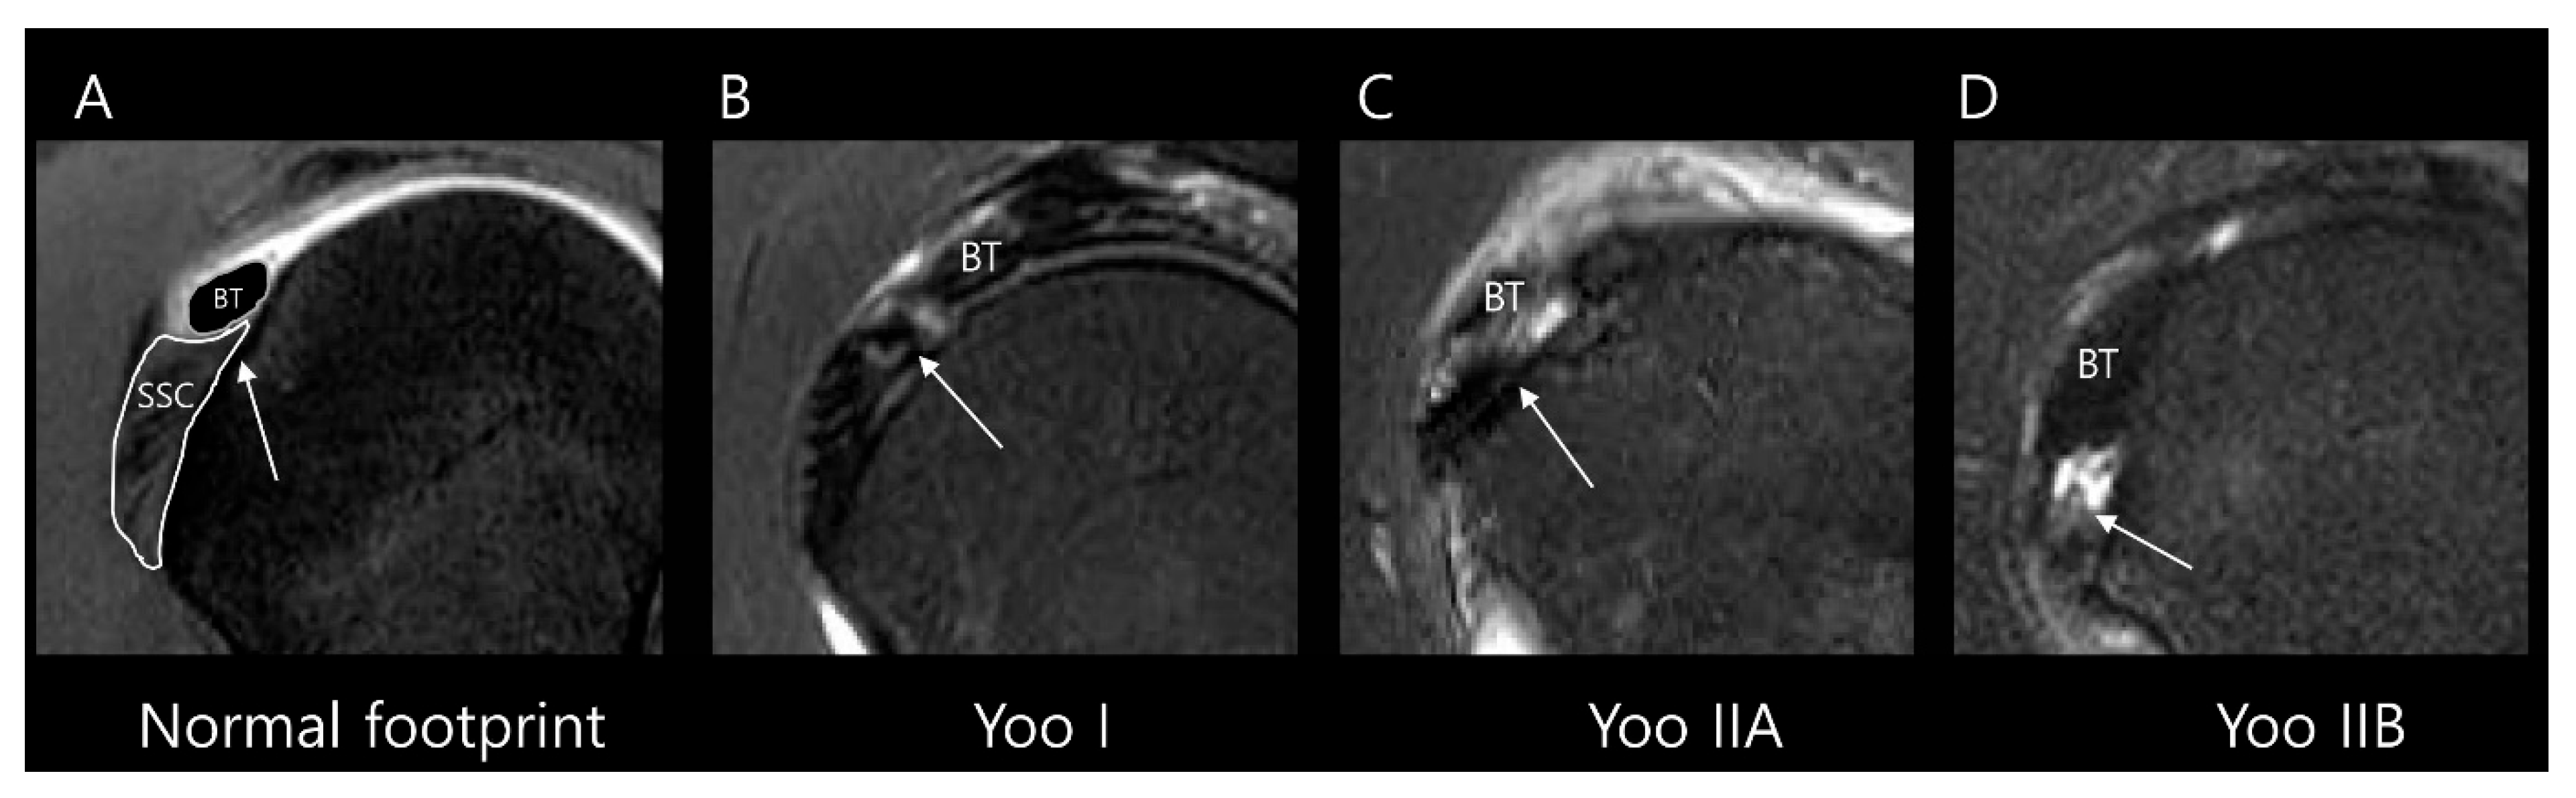

Fatty infiltration for the subscapularis muscle was assessed using the modified Goutallier method proposed by Yoon et al. [14]. In this system, the degree of fatty infiltration is graded separately for the upper and lower portions of the muscle (Table 2). Representative MRI examples of each modified Goutallier grade are presented in Figure 5. For statistical analysis, we categorized fatty infiltration into two categories: grade 0–1 and grade 2–3. No cases in this study showed grade 4 or higher fatty infiltration.

Figure 5.

Evaluation of subscapularis muscle fatty infiltration on T2-weighted oblique sagittal images according to the modified Goutallier method [14]: (A) Grade 0: no fat. (B) Grade 1: some fatty streaks. (C) Grade 2: less fat than muscle in the upper half of the muscle. (D) Grade 3: more fat than muscle in the upper half of the muscle, with normal or fatty streaks in the lower half of the muscle. (E) Grade 4: more fat than muscle in the upper half of the muscle, with less fat than muscle in the lower half of the muscle. (F) Grade 5: more fat than muscle in the upper and lower halves of the muscle.